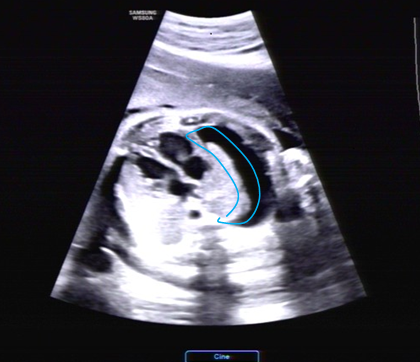

近日,懷孕38周的劉女士在當(dāng)?shù)禺a(chǎn)檢時發(fā)現(xiàn)胎兒右側(cè)大量胸腔積液,右側(cè)胸腔幾乎被“水”填滿,輾轉(zhuǎn)當(dāng)?shù)囟嗉裔t(yī)院均認(rèn)為預(yù)后不良,建議放棄胎兒。

經(jīng)過評估,劉女士的寶寶屬于孕晚期突發(fā)的單側(cè)大量胸腔積液,已經(jīng)對胎兒心臟和肺產(chǎn)生了壓迫,如不及時解決,后續(xù)胎兒可能出現(xiàn)水腫,隨時有生命危險。

先天性乳糜胸是由各種原因?qū)е碌男啬V過壓力增高、淋巴引流受阻及淋巴管通透性增加而引起淋巴液漏出到胸膜腔內(nèi),常見病因包括胸導(dǎo)管發(fā)育異常、先天性淋巴管擴(kuò)張、淋巴管發(fā)育不良、淋巴管瘺等。導(dǎo)致胎兒不良預(yù)后的原因通常是大量胸腔積液壓迫心臟和肺引起胎兒呼吸和循環(huán)系統(tǒng)衰竭。